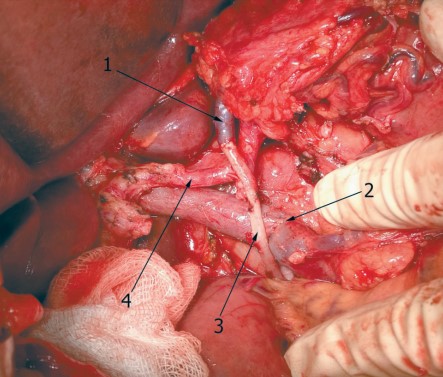

3. Рис. 3. TП с ПВР: 1 – левая желудочная вена; 2 – портомезентериальный анастомоз; 3 – правая гонадная вена; 4 – печеночная артерия. Примечание: рисунок выполнен авторами | |